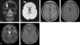

Metastasis to skull

Bone metastases, or osseous metastatic disease, is a category of cancer metastases that results from primary tumor invasion to bone. Bone-originating primary tumors such as osteosarcoma, chondrosarcoma, and Ewing's sarcoma are rare. [Source: Wikipedia ]